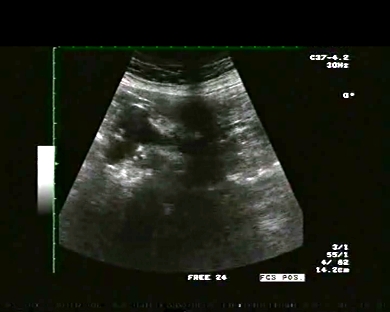

Data inserimento: 07/10/2009

Ecografia del: 15/05/2009

Strumento: Toshiba 380A

Sonda: Convex 3,5 Mhz

Età paziente: M 63 anni

Motivazione dell'esame: il paziente si sottopone ad indagine ecografica per colica addominale occorsa 4 giorni prima.

Commento all'esame: le immagini ed il video documentano la colecisti molto distesa con  diametro longitudinale massimo 91 x 42 mm (idrope della colecisti  se diametro logitudinale  >10 mm  e trasverso >50 mm)  e con sludge biliare. Le vie biliari intra ed extraepatiche sono normali. il rene destro  in sede, con diametro bipolare di 119 mm ed evidenza di grossa cisti di 61 x 67 mm in sede mesorenale  che arriva all'infundibolo e corpo della colecisti. Indispensabile il follow-up, la valutazione gastroenterologica-chirurgica e clinica del medico curante. Potete esprimere le vostre osservazioni e commenti sul BLOG.

In collaborazione: Dr. Quintilio Tomassetti - Ancona

Presentazione: Dr. Massimo Dolciotti - Ancona